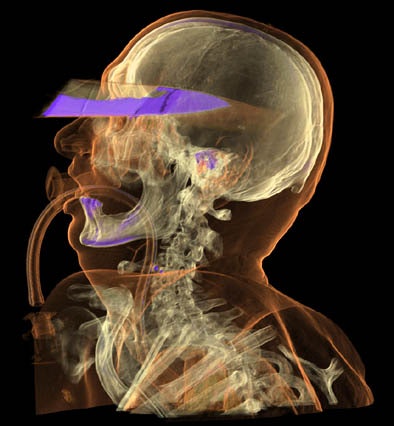

As for CT, its speed, subtle grayscale, and ability to depict 3D relationships are enormous advantages. Skeletal trauma, for example, can be depicted in ways that conventional autopsy can't replicate.

A close look at the 3D reconstructions can often separate a mortal wound from nonfatal trauma that only looks deadly, which makes the modality indispensable in forensic examinations, Volk said.

The wrong conclusions surrounding the 1963 assassination of U.S. President John F. Kennedy would certainly have benefited from 3D visualization, Thali said of the infamous autopsy that was plagued (at the very least) by the limitations of poor documentation and 2D photography.

Thus, he suggested, if today's 3D imaging techniques had been available, the "magic bullet theory" (which posits that a single bullet caused all of the nonfatal wounds in both President Kennedy and then Texas Governor John Connally) might have died a very quick death.

Overall, "CT is an excellent tool for the documentation of bone defects and the detection of pathological air or gas in the body, and it's an excellent tool for 2D or 3D reconstruction," Thali said. In cases of mass deaths, dental CT records can be enormously helpful in identifying victims.